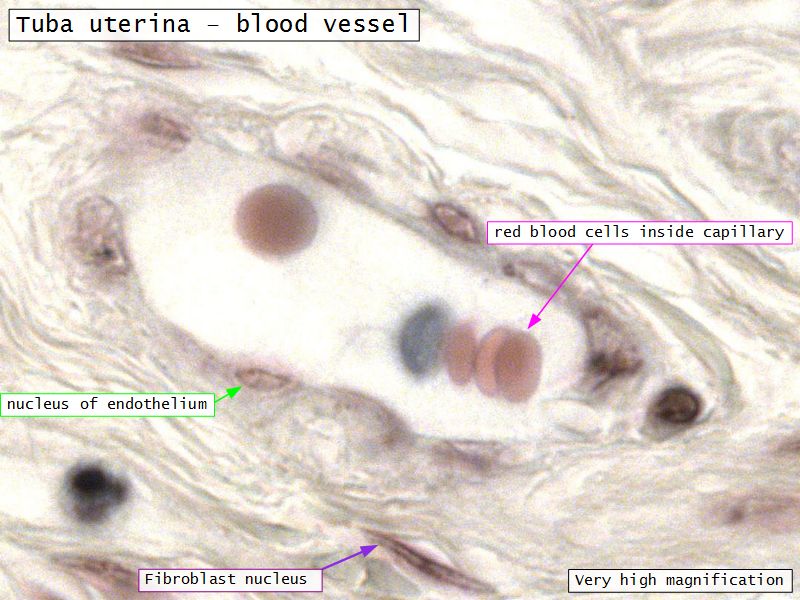

Tuba uterina

Tuba uterina

- Muscular tube

- Most frequent site of fertilization

- Conveys zygote to uterus

- Four regions

- Three layers

Three layers

- Mucosa

- Muscular layer

- Serosa

Lamina propria

- Loose connective tissue

- Reticular fibres

- Fibroblasts

- Mast cells

- Lymphoid cells